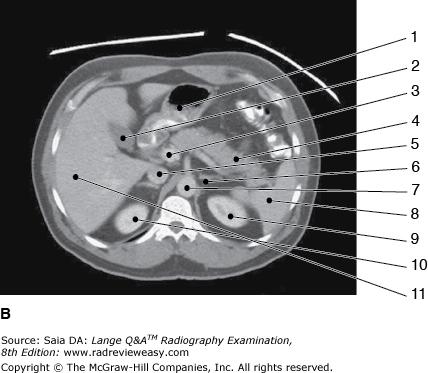

Which of the following is represented by the number 3 in the figure below?

Aorta

The structure labeled number 2 in Figure 6–3, image B is the

gallbladder

Which of the following statements is (are) true with regard to the two CT images seen below?

- Image A illustrates more superior structures.

- The images are sagittal reconstructions.

- The exam was performed without artificial contrast.

1 only